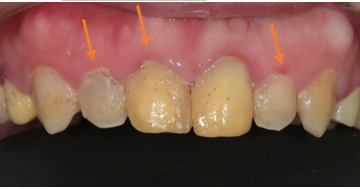

治療前:前牙臨時牙套顏色蠟黃,齒色不均。

治療後 :牙冠增長術修整牙齦+貼片覆蓋,修飾牙齒形狀及顏色,

牙齦覆蓋牙齒較多,笑齦。

笑齦改善,閃亮亮的白牙出現啦。